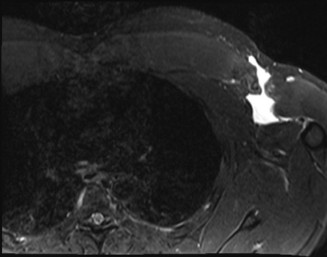

A 45-year-old carpenter presents with shoulder pain that has been ongoing for the last 3 months. He denies any significant injury. He describes night pain and significant discomfort at work. His imaging is shown in Figure 2–9. What is the most likely diagnosis?

🔍 Click to enlargeClinical Radiograph / Orthopedic Image

Figure 2–9_From Shi LL, Mullen MG, Freehill MT, et al. Accuracy of Long Head of the Biceps Subluxation as a Predictor for Subscapularis Tears. _Arthroscopy 2015;32(4):615–619.

Discussion

The correct answer is (A). Medial subluxation of the biceps tendon as seen in this MRI is commonly associated with a tear of the subscapularis tendon which attaches to the lesser tuberosity. This patient’s pain may in part be attributable to the subscapular tear and this should be evaluated for during physical examination. Supraspinatus tears (Answer B) cannot be easily visualized on axial views and are not associated with medial biceps subluxations. A labral tear and ALPSA lesion (Answers C and D) are not seen on the images provided. The question stem and MRI are not suggestive of shoulder instability (Answer E). Objectives: Did you learn...? Diagnose and treat acute rotator cuff tears?